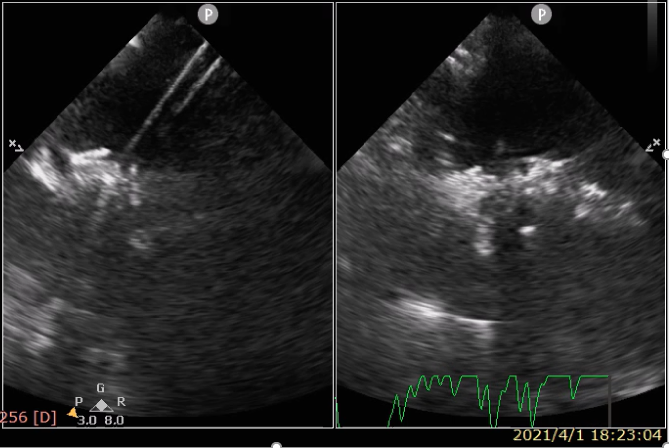

本次患者是个中年女性,体检发现房间隔缺损,大小18mm,选用ReAces 24mm封堵器,手术顺利完成,术后心超显示封堵器成形、贴合良好,封堵器内及边缘无残余分流。术中影像分析还发现,该器械具有另外一个比以往封堵器更优势的特点,由于双盘面是开放性设计,双盘和房间隔之间更服帖,有望加速器械内皮化。ReAces封堵器是葛均波院士结构团队继全球首个经心尖二尖瓣夹合器ValveClamp之后发明的第二个走向临床的全球首创医疗器械。